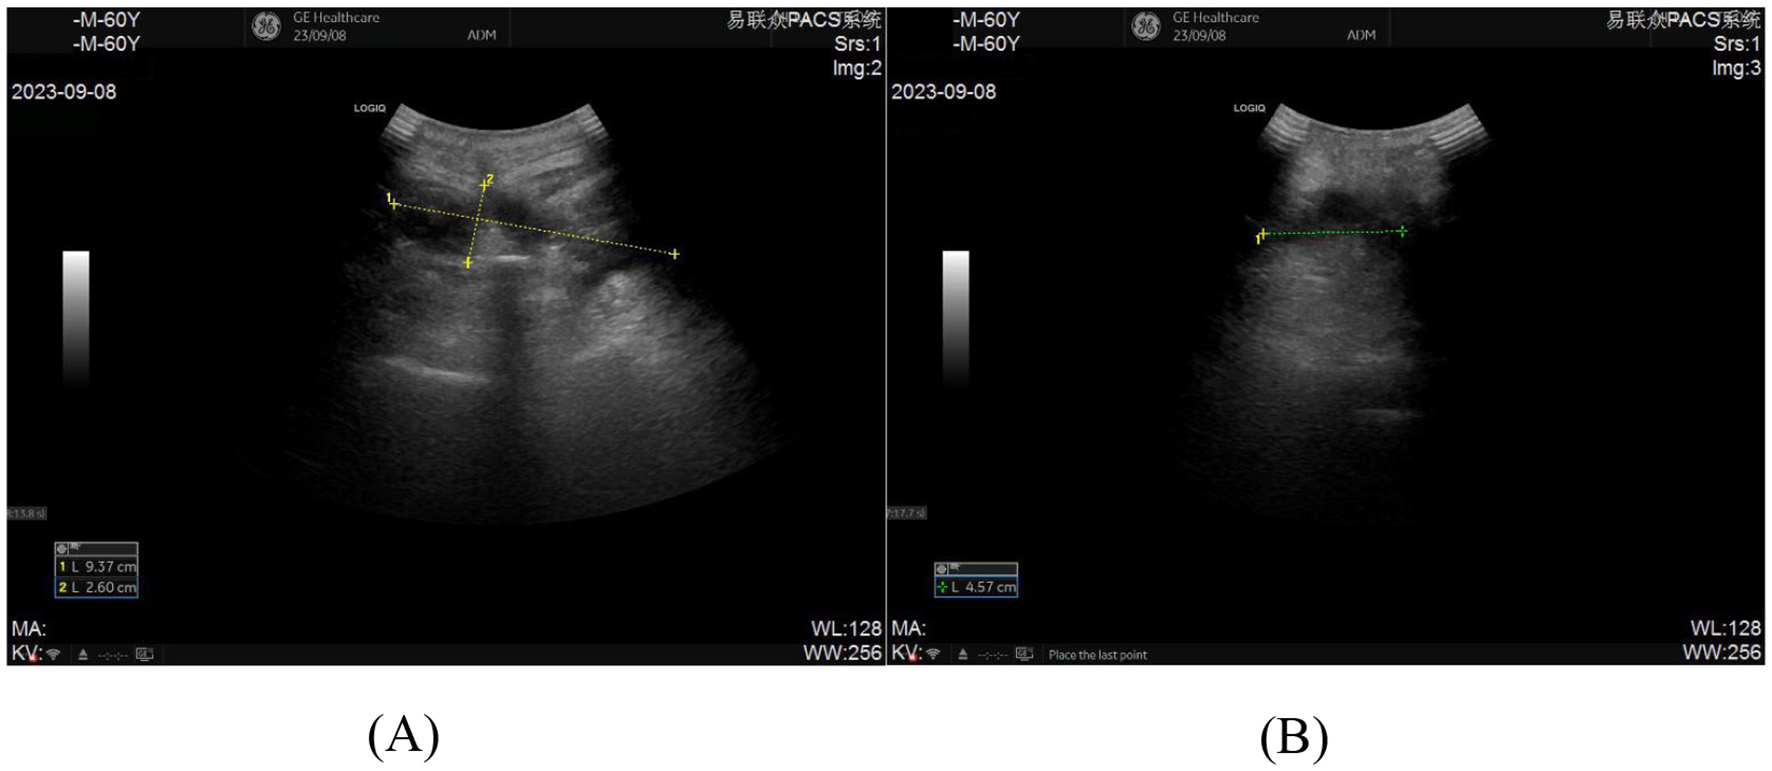

On postoperative day 12, the patient developed fever with occasional cough. A dressing change revealed no signs of erythema, swelling, heat, or pain at the incision site, which exhibited satisfactory healing. Laboratory tests showed leukocytosis (14.21 × 109/L) and elevated C-reactive protein (104.22 mg/L). The symptoms were initially attributed to aspiration pneumonia secondary to drowning. Prompted by this suspicion, cefathiamidine antibiotic therapy was initiated. However, after 3 days of treatment, the patient remained febrile with persistent cough and developed cervicodorsal pain. Repeat laboratory tests demonstrated decreased leukocyte count (10.42 × 109/L) but further elevated inflammatory markers (C-reactive protein: 205.31 mg/L; erythrocyte sedimentation rate: 82.00 mm/h). Suspecting surgical site infection, the incision was re-evaluated, revealing minimal serous discharge at the distal drainage orifice (Figure 1), and subsequent ultrasonography identified a deep encapsulated fluid collection (9.37 cm × 2.60 cm × 4.57 cm) within the surgical field, confirming the diagnosis of postoperative infection (Figures 2A, B).

Figure 2

(A, B) Pre-procedural ultrasonographic imaging of the incision for ultrasound-guided percutaneous catheter drainage demonstrates an abscess measuring 9.37 cm × 2.60 cm × 4.57 cm.